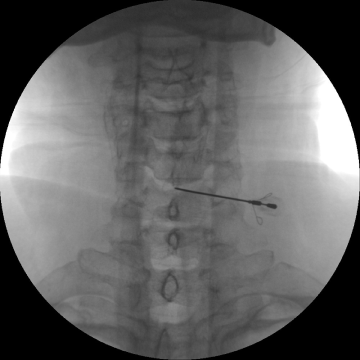

시술

고주파수핵성형술

2017.08.07